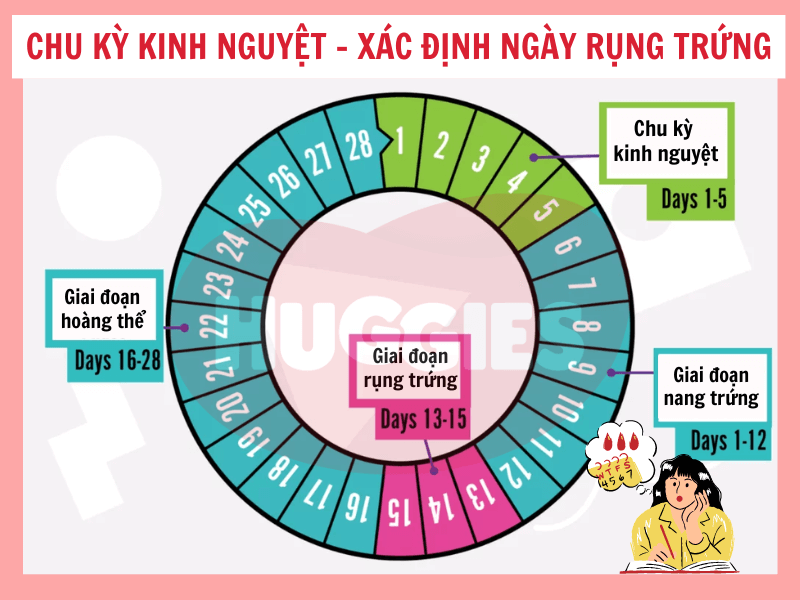

- Tin vào “tính ngày an toàn” nhưng chưa hiểu rõ cơ chế rụng trứng

- Tính ngày rụng trứng: Cần theo dõi chu kỳ kỹ lưỡng và không phù hợp với người có chu kỳ không đều.

Chào bạn thân mến, bạn có bao giờ tự hỏi làm thế nào để tính thời gian rụng trứng một cách chính xác nhất không? Việc hiểu rõ chu kỳ rụng trứng của bản thân không chỉ là kiến thức quan trọng về sức khỏe giới tính, mà còn là một cách tuyệt vời để […]

Chào bạn yêu quý, chúng ta lại gặp nhau rồi. Hôm nay, chúng ta sẽ cùng nhau trò chuyện về một chủ đề rất được quan tâm, đặc biệt là với những ai đang mong muốn chào đón một thành viên mới trong gia đình: đó là cách tính ngày rụng trứng thụ thai. Hiểu […]

Chào bạn thân mến, Tại Chuyenseg, chúng mình hiểu rằng hành trình khám phá và làm chủ cơ thể mình là một điều vô cùng thú vị và quan trọng. Đặc biệt, việc tính ngày rụng trứng chính xác là một trong những kiến thức nền tảng giúp bạn hiểu sâu hơn về chu kỳ […]